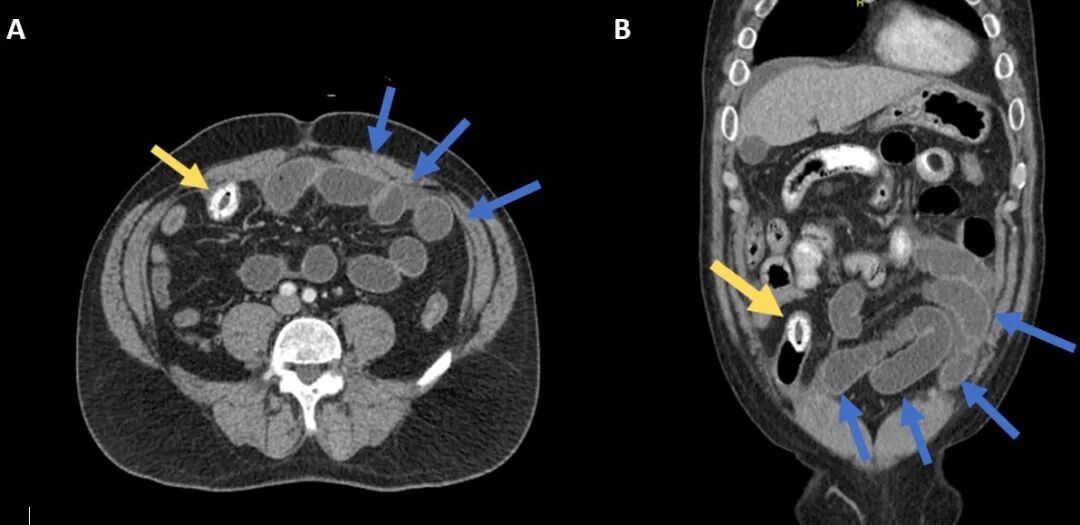

腹部增强CT显示:远端回肠管腔内有一团3cm的高密度影,中心为低密度区,近端肠管扩张伴远端肠管塌陷,无胆道积气或胆囊壁增厚的征象(图1)。肝区超声检查未发现任何瘘管或胆结石。

图1:腹部CT